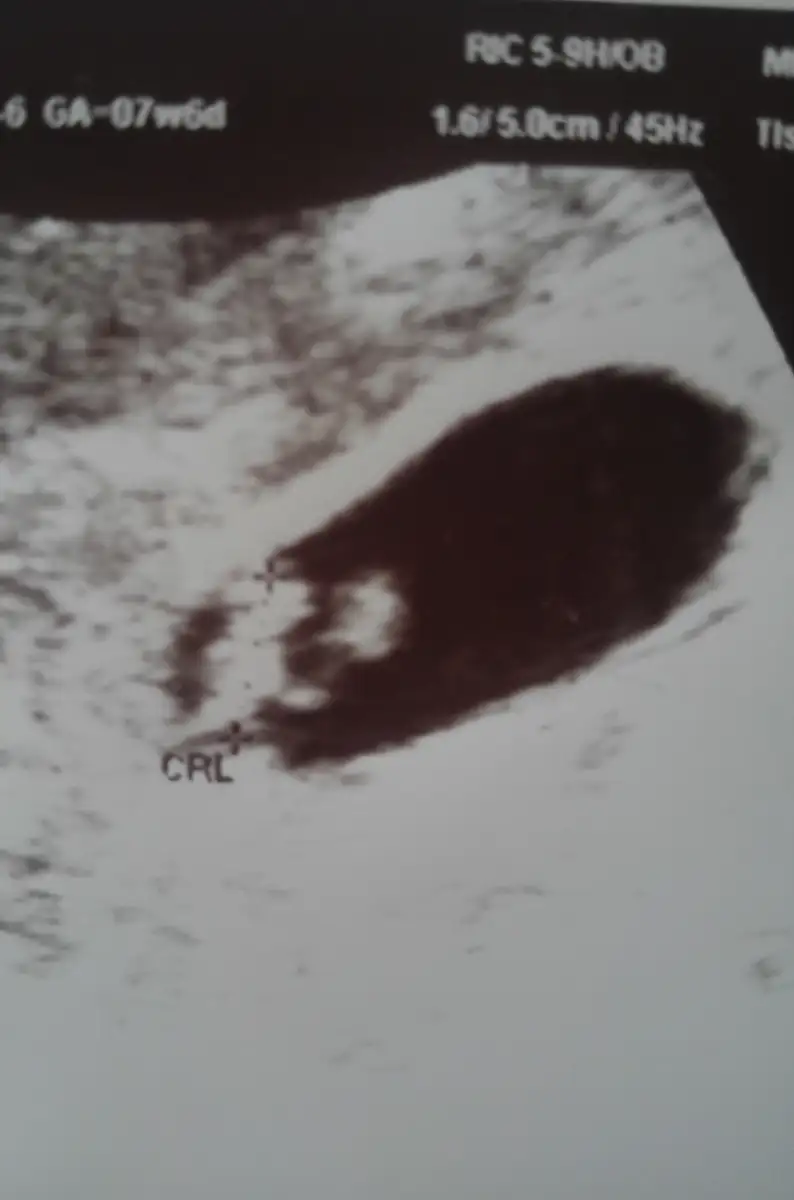

Resmin ekran görüntüsü al o ekran görüntüsünü yükle canımBu arada bu da minigim.

Poz verdi bize cok güldük:))